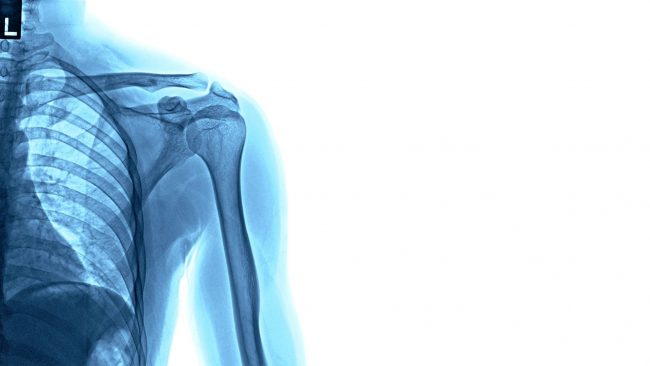

Röntgen (benannt nach dem Physiker Wilhelm Conrad Röntgen), auch Röntgendiagnostik genannt, ist ein weit verbreitetes, bildgebendes Verfahren, bei dem der Körper unter Verwendung eines Röntgenstrahles durchstrahlt wird. Röntgenstrahlen können zur Darstellung von Körperstrukturen wie Knochen, Gefäße und innere Organe verwendet werden. Seit Entdeckung der Röntgenstrahlen wurde das Verfahren permanent weiterentwickelt und in nahezu allen Bereichen der…